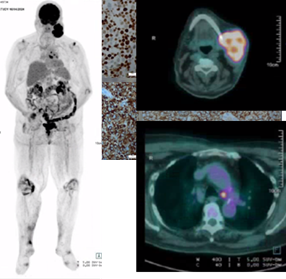

Por haver suspeita de alergia ao contraste, não realizou TC tóraco-abdómino-pélvica (TAP), tendo efetuado uma Tomografia por Emissão de Positrões com fluorodesoxiglicose (PET-FDG) para estadiamento da doença. A PET-FDG identificou “volumosa massa hipermetabólica (SUV máximo = 13,8 com áreas hipometabólicas centrais, sugestivas de necrose) em localização cervical esquerda (não se excluindo extensão ao ramo mandibular esquerdo, de difícil individualização pelo presente método), já conhecida e compatível com malignidade. Individualizam-se, também, focos hipermetabólicos em localização para-traqueal inferior esquerda (SUV máximo = 6,4), infra-carinal (SUV máximo = 7,9) e bronco-hilar esquerda (SUV máximo = 4,1), igualmente suspeitos de etiologia maligna, neste contexto” (Figs. 16, 17 e 18).

Figs. 16, 17 e 18 : PET-FDG - Atividade hipermetabólica em massa cervical esquerda e gânglios para-traqueal, infra-carinal e bronco-hilar esquerdos.